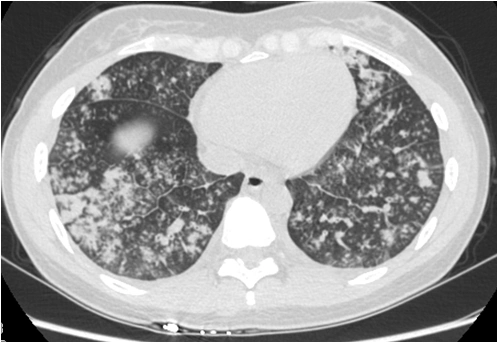

34 岁男性,继发于α1- 抗 胰蛋白酶缺乏症的全小叶型肺气肿患者